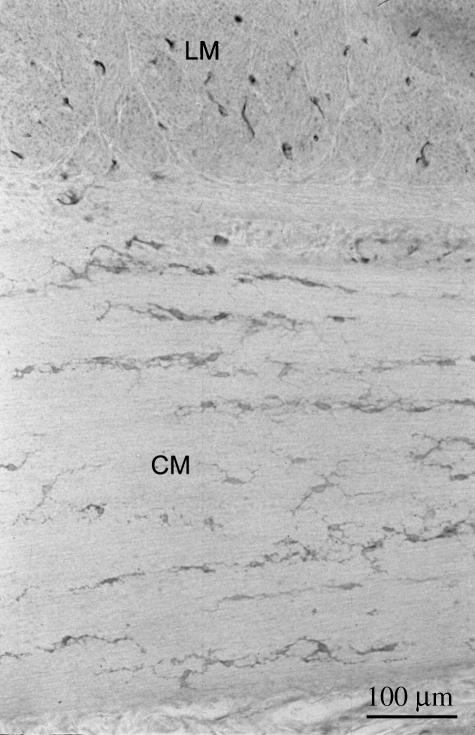

Fig. 1.

c-Kit immunoreactivity in the ileum of the small intestine in three fetuses, at 6 months (A), 7 months (B) and 10 months (C) of gestation. Individual c-Kit-immunoreactive ICC can be observed in both the myenteric plexus region and the circular muscle layer (arrows). LM, longitudinal muscle layer; CM, circular muscle layer; MG, myenteric ganglia.

In the small intestine (ileum) of all the fetuses examined, c-Kit-immunoreactive ICC were identified in the myenteric plexus region displaying a mixture of bipolar- and stellate-shaped morphologies. Individual ICC could be identified in the youngest fetuses but, in contrast, in the older fetuses and foals, the increasingly dense ICC network that developed surrounding the myenteric ganglia made it more difficult to identify individual cells (Figs 1 and 2). There was a limited and inconsistent degree of branching of ICC from the myenteric plexus region into the longitudinal muscle layer in the fetuses. However, this branching became more prominent and consistent in the neonates (Fig. 2).

Interstitial cells were also observed in the small intestinal circular muscular layer (Figs 1 and 2) in all samples. In the youngest fetus (6 months of gestation), few cells were observed within this muscle layer compared with the older fetus and neonate (Figs 1 and 2). The majority of ICC in the circular muscle of the ileum were bipolar in shape, although in the older fetus there appeared to be a slight increase in the proportion of stellate-shaped cells. The orientation of the long axis of ICC was parallel to the circular muscle fibres.